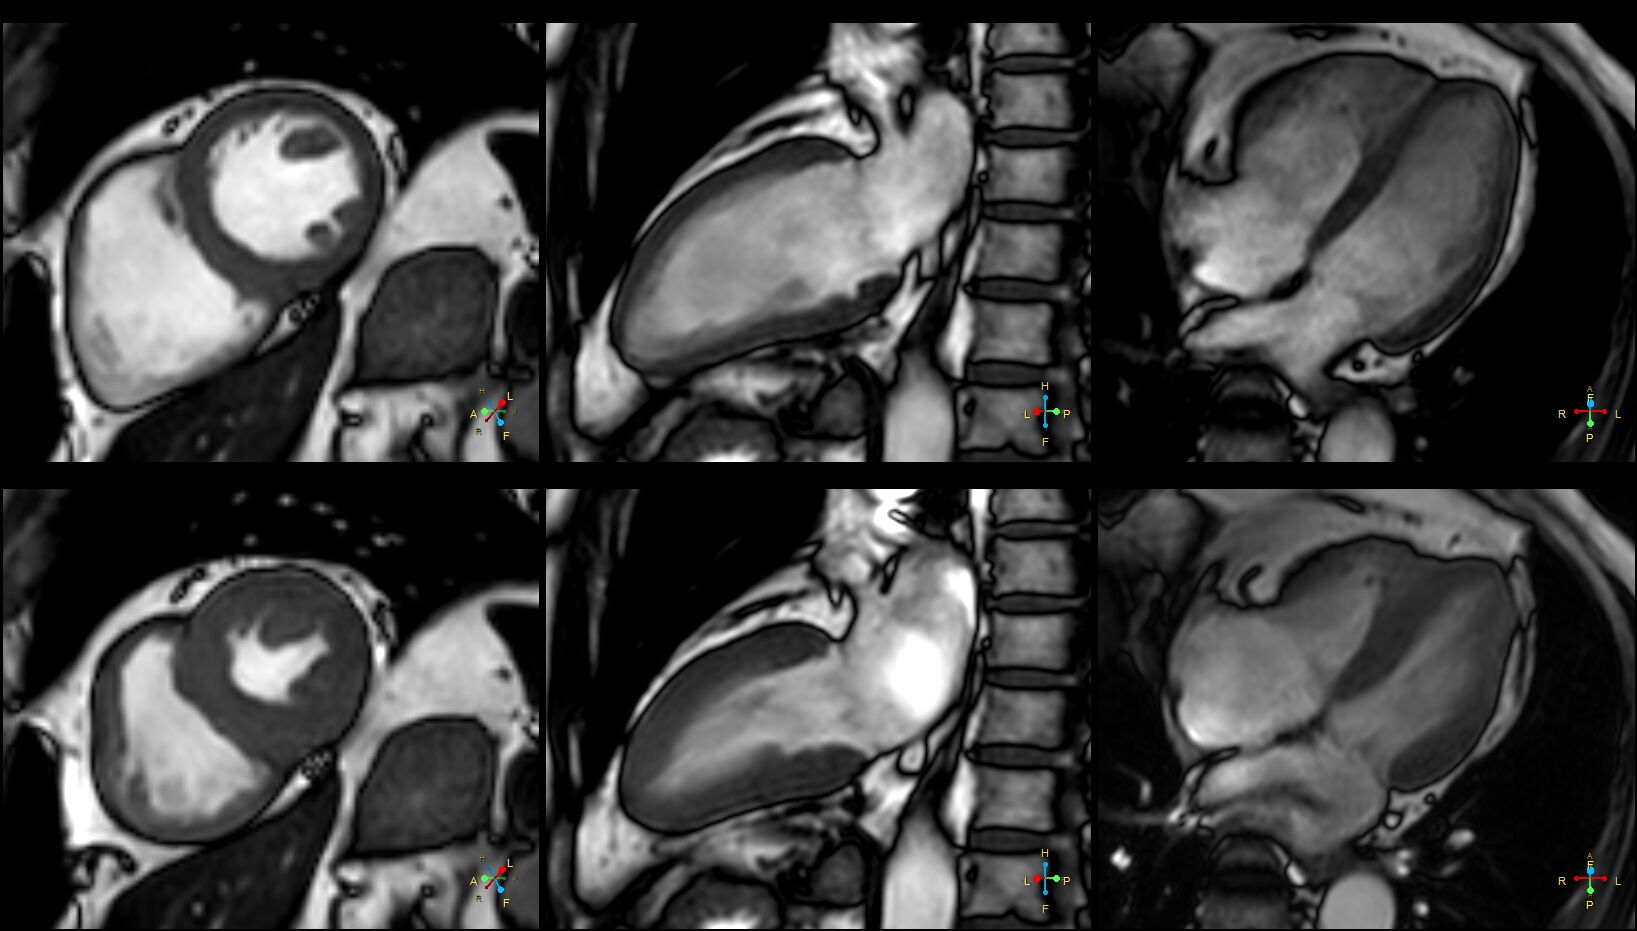

(Structure , Function)Cine , 動態影片,可以切出你想看結構,主要有4CH ,2CH ,SA, 2Ch , LVOT , RVOT ,Aortic valve ,R-2ch